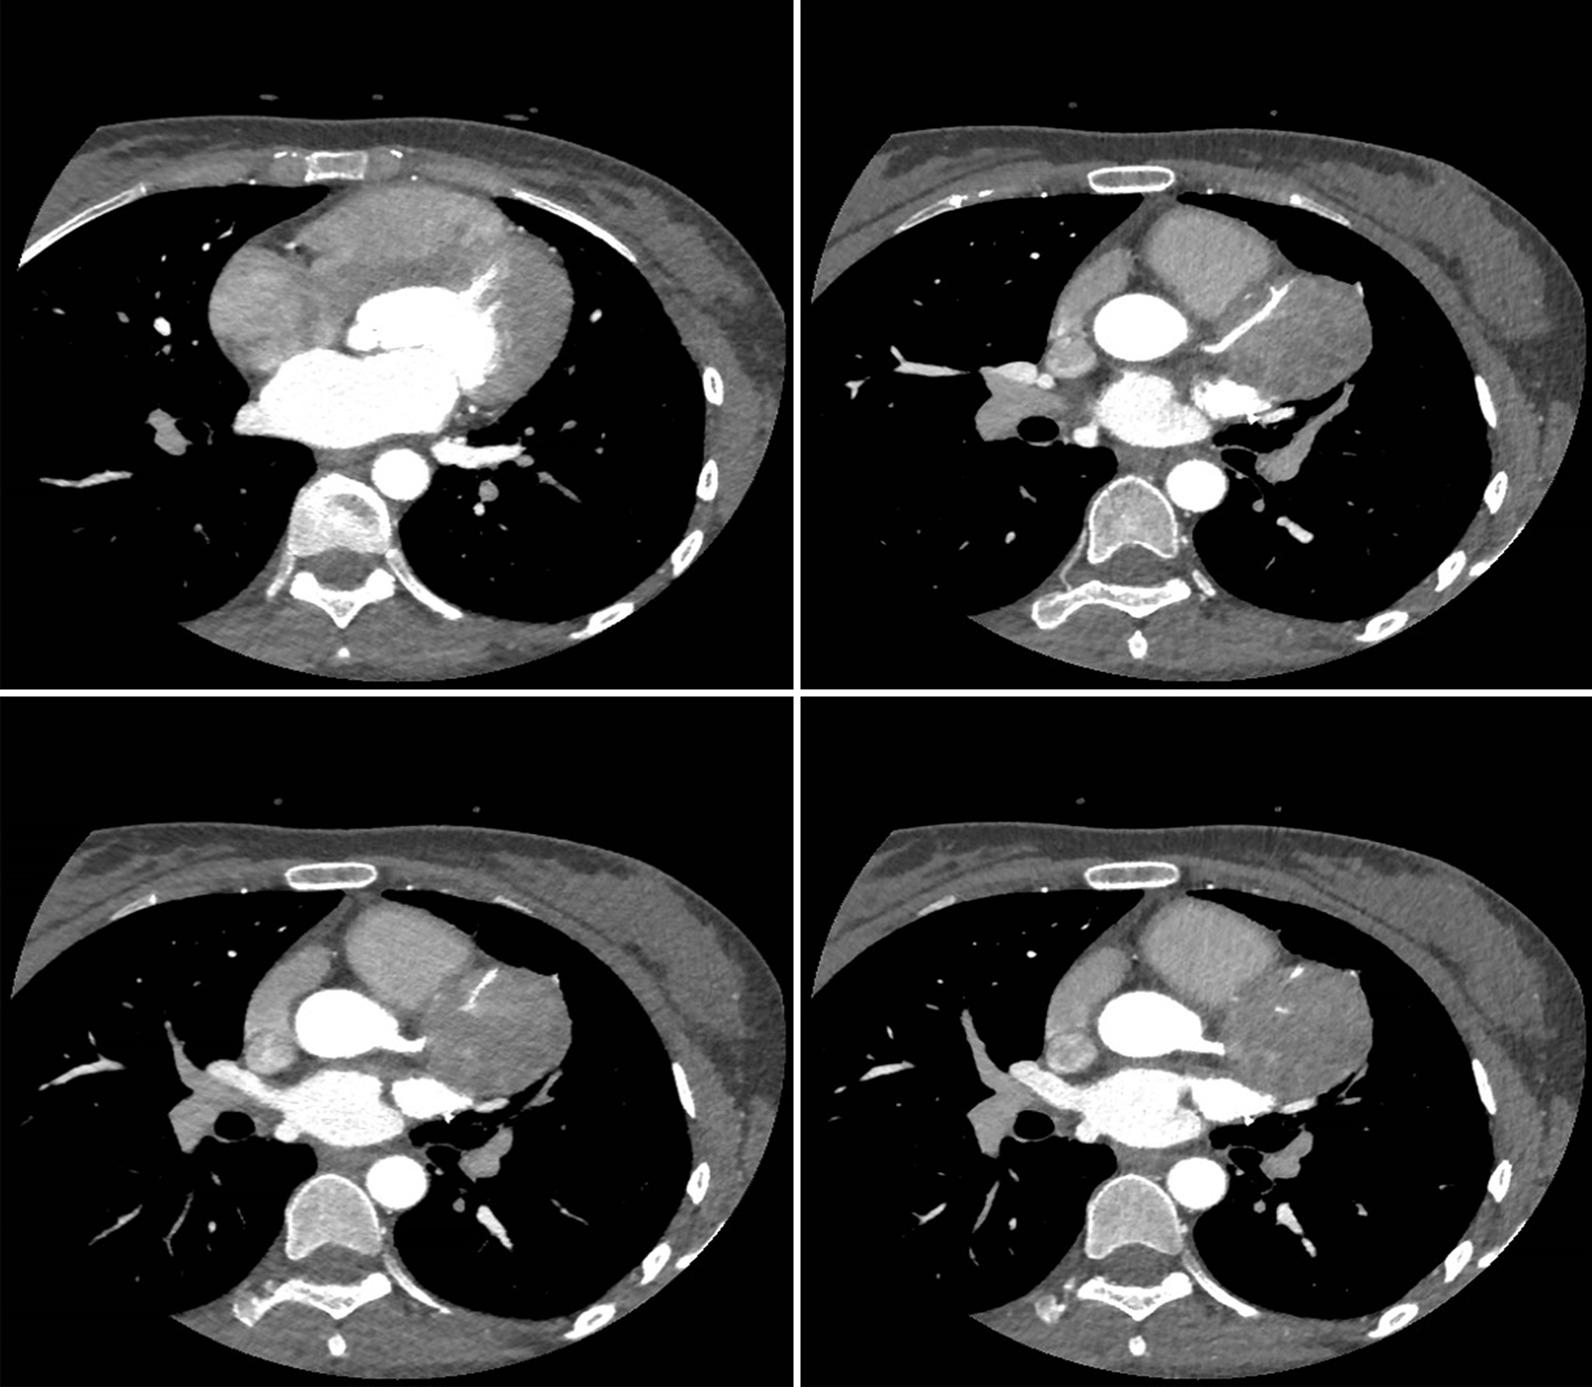

A 23-year-old woman presented with cough and progressive dyspnea for 1 month, followed by eyelid and facial edema for 10 days, without any apparent cause. Significantly elevated tumor markers were detected in her blood. A cardiac ultrasound revealed a 74 mm × 61 mm spherical mass that was attached to the left pericardium, as well as massive pericardial effusion. Positron emission tomography-CT (PET-CT) showed focal hypermetabolism in the left pericardium. Via histopathology and immunohistochemistry, the spherical mass was identified as PNETS. The patient was successfully treated with a combination of surgical resection via thoracotomy and postoperative chemotherapy, and she was disease-free for 7 years at follow-up. Unfortunately, at 7 years after the treatment, the patient's pPNET recurred. Positron emission tomography-MRI (PET-MRI) and 64-slice coronary CTA revealed that the aorta and multiple coronary arteries were involved. Subsequently, the patient refused a heart transplant and voluntarily left the hospital.

一名 23 岁女性因咳嗽和进行性呼吸困难 1 个月,随后出现眼睑和面部水肿 10 天,无明显诱因就诊。血液中明显升高的肿瘤标志物。心脏超声显示左心包附着的 74mm×61mm 球形肿块和大量心包积液。正电子发射断层扫描-CT(PET-CT)显示左心包局灶性高代谢。通过组织病理学和免疫组织化学,球形肿块被确定为 PNETS。患者通过开胸手术联合术后化疗成功治疗,随访 7 年无病。不幸的是,治疗 7 年后,患者的 pPNET 复发。正电子发射断层扫描-MRI(PET-MRI)和 64 层冠状动脉 CTA 显示主动脉和多支冠状动脉受累。随后,患者拒绝心脏移植并自愿出院。